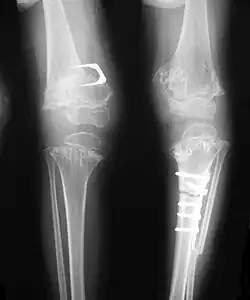

| Pseudoachondroplasia. Shoulder and humerus. Note the dysplastic proximal humeral epiphysis, metaphyseal broadening, irregularity and metaphyseal line of ossification. These changes are collectively known as "rachitic-like changes". Lesions are bilateral and symmetrical. | |

Skeletal radiography

Accurate assessment of plain radiographic findings remains an important contributor to diagnosis of pseudoachondroplasia. It is noteworthy that vertebral radiographic abnormalities tend to resolve over time. Epiphyseal abnormalities tend to run a progressive course. Patients usually suffer early-onset arthritis of hips and knees. Many unique skeletal radiographic abnormalities of patients with pseudoachondroplasia have been reported in the literature.[2][7][4]

- Together with rhizomelic limb shortening, the presence of epiphyseal-metaphyseal changes of the long bones is a distinctive radiologic feature of pseudoachondroplasia.

- Dysplastic/hypoplastic epiphyses especially of shoulders and around the knees.

- Metaphyseal broadening, irregularity and metaphyseal line of ossification. These abnormalities that are typically encountered in proximal humerus and around the knees are collectively known as "rachitic-like changes".

- Radiographic lesions of the appendicular skeleton are typically bilateral and symmetric.